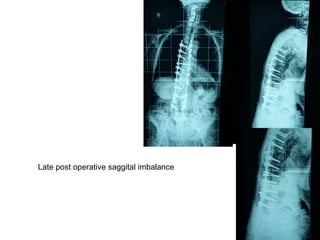

Late post operative saggital imbalance

Treatment

• Osteotomy L3 vertebra

• Spondylodesia’s extension to Sacrum - Ilium

Lumbar lordosis and saggital balance restoration